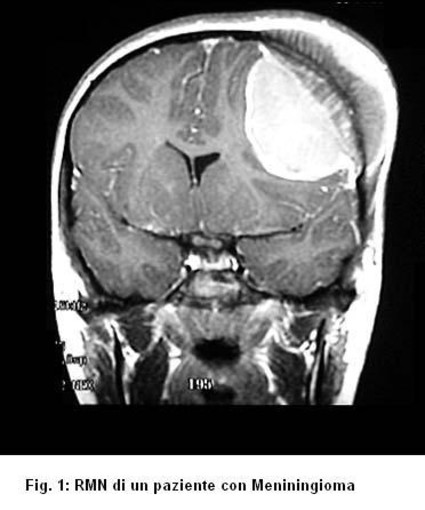

Il meningioma (Fig. 1) è una neoplasia benigna che origina da alcuni tipi di cellule presenti nelle meningi, cioè gli involucri del cervello e del midollo spinale. I meningiomi presentano un’età di incidenza massima tra i 40 e i 60 anni. Rappresentano il 15-20% di tutti i tumori endocranici ed il 25% di quelli spinali. Si manifestano prevalentemente nelle donne con un rapporto di 2:1 rispetto agli uomini. Solitamente non infiltrano il tessuto cerebrale e nella maggior parte dei casi possono essere rimossi senza danni. Altre volte si presentano strettamente aderenti alle strutture arteriose, venose e nervose: in questi casi la rimozione del tumore può risultare maggiormente problematica. Raramente un meningioma può essere maligno.

La diagnosi, supportata da un iniziale sospetto clinico, viene strumentalmente eseguita con la TC e/o la Risonanza Magnetica Nucleare.

La RM è l’esame diagnostico di scelta per una migliore accuratezza dei dettagli rispetto alla TC e risulta indispensabile per una eventuale pianificazione dell’intervento chirurgico. La TC rimane, comunque, un esame complementare di fondamentale importanza poiché, al contrario della RMN, chiarisce il grado di coinvolgimento osseo delle strutture craniche frequentemente riscontrato nei meningiomi. La somministrazione del mezzo di contrasto, sia alla TC che alla RM favorisce una migliore visibilità del tumore rispetto al parenchima cerebrale circostante e permette di chiarirne i rapporti con le strutture neuro-vascolari coinvolte o vicine. Sia la TC che la RM dimostrano bene l'edema (presente nel 50% circa dei casi), ossia il rigonfiamento reattivo del tessuto nervoso che contribuisce marcatamente alle manifestazioni sintomatiche. Nel caso dei meningiomi cerebrali è di fondamentale importanza chiarire il rapporto del tumore con le arterie e le vene vicine. Il mezzo migliore a questo scopo è l'Angiografia Cerebrale, esame che può essere eseguito solo in regime di ricovero. Questo esame seppur invasivo rappresenta, inoltre, un valido strumento nella strategia chirurgica di rimozione poichè consente in alcuni selezionati casi di obliterare i principali vasi nutritizi del tumore, facilitandone la successiva rimozione chirurgica. Ciò si traduce in un più agevole intervento per il neurochirurgo e in una minore perdita ematica per il paziente con un più rapido recupero post-operatorio.